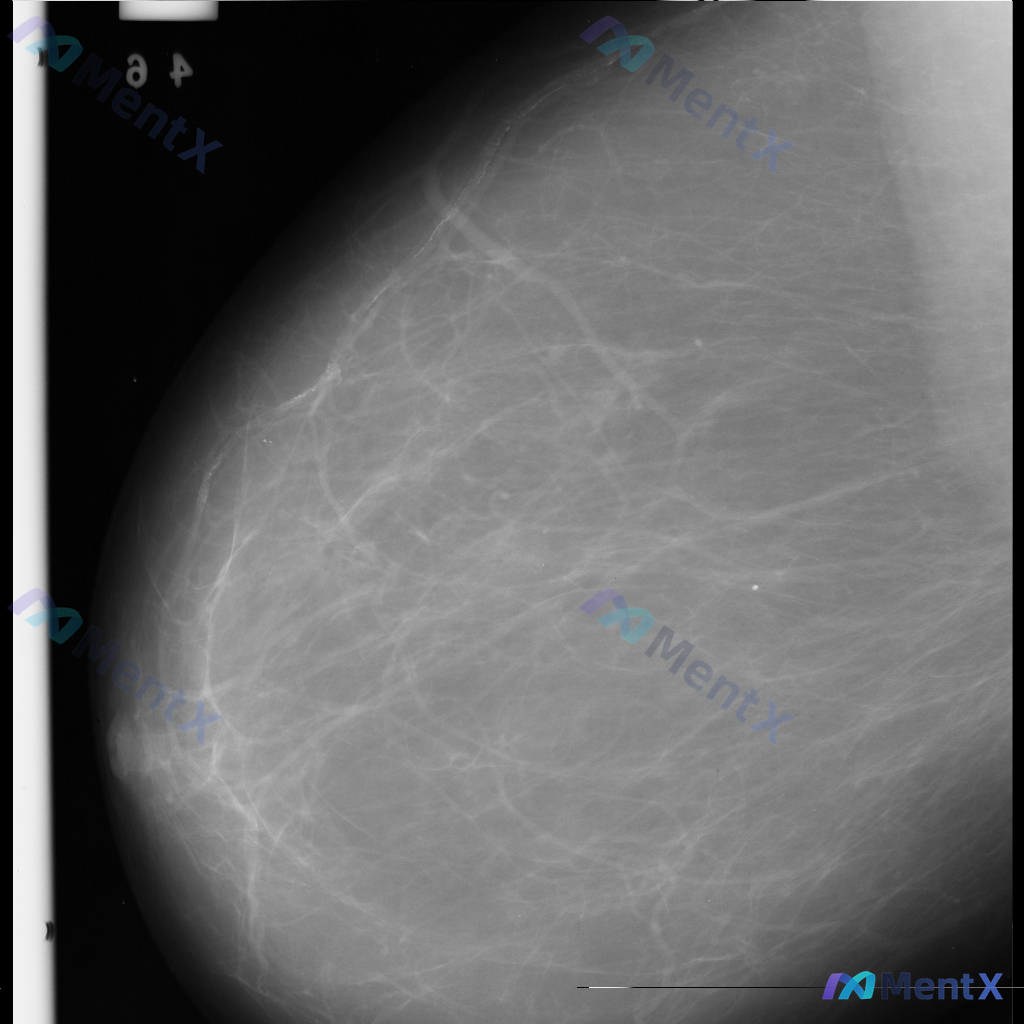

整理到一张乳腺钼靶影像资料,大家一起讨论下。 影像表现大概是这样: - 异常区域位于乳腺下象限偏外侧 - 可见一局限性致密影,形态大致呈卵圆形或不规则形 - 边缘部分清晰,局部可能模糊或有细微毛刺样改变 - 致密影密度高于周围脂肪组织,与纤维腺体组织密度相似或略高 - 周围乳腺小梁结构似有轻微的牵拉...